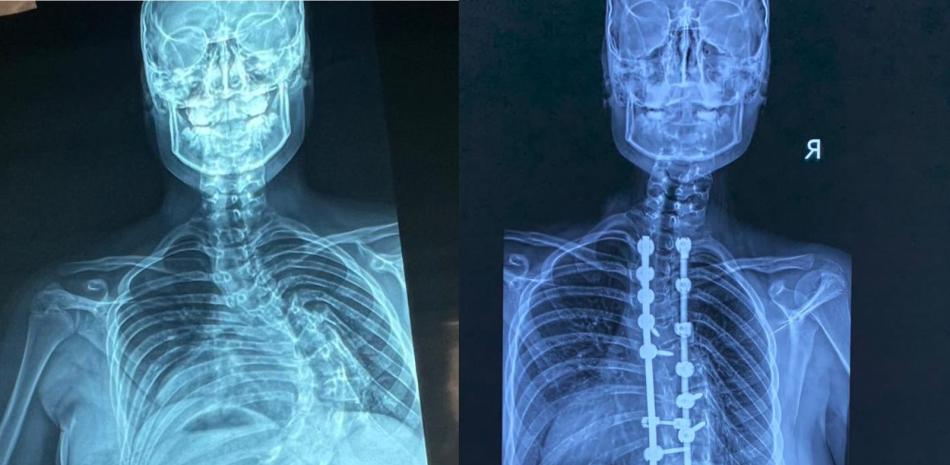

En los últimos cuatro años, se han llevado a cabo cerca de 350 intervenciones quirúrgicas para corregir deformidades en la columna vertebral pediátrica en República Dominicana, específicamente en el hospital Robert Reid Cabral y en la Sociedad Dominicana de Rehabilitación, bajo la coordinación del doctor Carlos Rodríguez Estévez, quien preside la Sociedad Dominicana de Cirugía de Columna.

En la unidad especializada en escoliosis del Hospital Infantil Robert Reid Cabral se han llevado a cabo más de 250 intervenciones para tratar esta afección, que afecta a numerosos niños y adolescentes en el país.

La escoliosis consiste en una desviación de la columna vertebral superior a 15 grados. El especialista explicó que la forma más común es la escoliosis idiopática del adolescente.